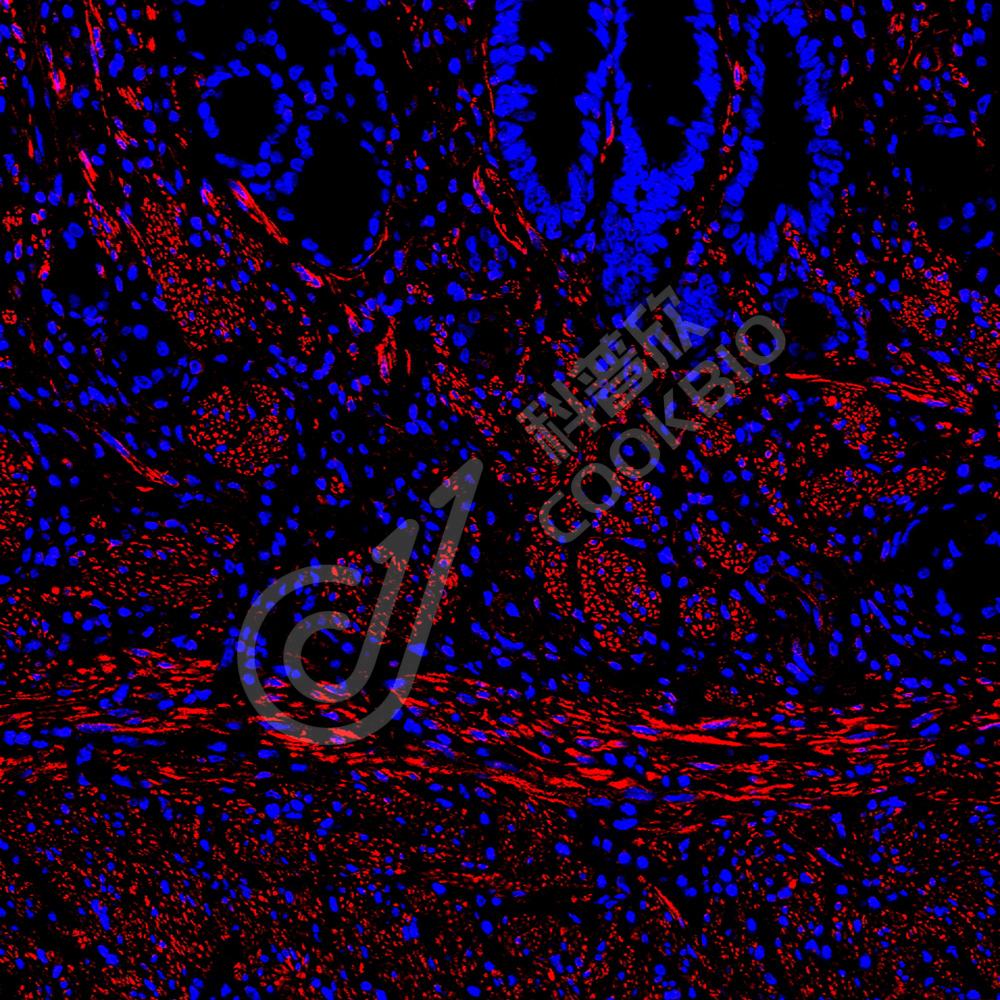

IF检测Desmin蛋白(货号 K236225)(红色).

样品: 人胃, 4%多聚甲醛 (货号KSG1101) 固定12-24小时.

抗原修复: 柠檬酸抗原修复液(干粉, pH 6.0) (KSG1201), 高压锅均匀喷气计时2分钟.

封闭: 3% BSA(货号KSGC305010)的PBS溶液, 室温孵育30分钟.

—抗: 1: 1300稀释, 4℃ 孵育过夜.

二抗: Cy3标记山羊抗小鼠IgG (H+L) (货号KB63903), 1: 300稀释, 室温孵育1小时.